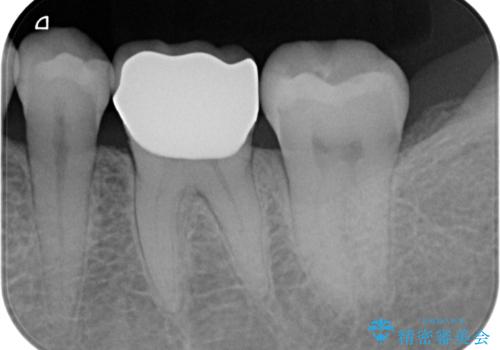

- 口の中に見える銀歯を、金属アレルギーの対策と審美性の向上のため全て除去したい!と希望され来院されました。

銀歯を丁寧に除去したのち、精度の良いセラミックインレー、セラミッククラウンで修復・補綴処置を行っていきます。

- 62.7万円(ジルコニアクラウン×3・仮歯×3・セラミックインレー×3)費用は治療当時の料金となります